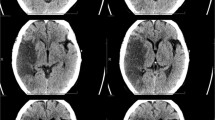

Neurological symptoms were also reported in SARS-CoV-1 and MERS-CoV patients, and included confusion, coma, ataxia, stroke, and focal motor deficits [8, 9]. Magnetic Resonance Imaging (MRI) in a select group of MERS-CoV patients revealed widespread bilateral lesions within the white matter, subcortical areas, basal ganglia, corpus callosum, pons, cerebellum and upper cervical spinal cord [9]. Autopsy studies of patients who died of SARS-CoV-1 confirmed the presence of the virus in the brain [33]. Solomon et al. recently described the post-mortem neuropathological changes associated with SARS-CoV-2 infection in 18 patients. They detected virus in low levels within the brain of several patients with pre-existing microvascular disease (e.g. diabetes, hypertension, cardiovascular disease), all of whom presented with encephalopathy [34]. Their work highlights the importance of pre-existing comorbidity in predisposing to acute hypoxic ischemic brain injury.

Adults infected with SARS-CoV-2 may develop acute encephalopathy and meningitis [21,22,23,24, 83], with neuroimaging evidence of microhemorrhages and diffuse inflammation of the white matter [79]. A case of SARS-CoV-2 infection was associated with acute hemorrhagic necrotizing encephalopathy (ANE) [84]. Encephalopathy has also been described among children infected with SARS-CoV-2 [30, 85]. Brain MRI changes in the splenium of the corpus callosum of pediatric patients infected with SARS-CoV-2 [30], are similar to those reported in children with Kawasaki disease [86]. Li et al. examined the CSF of 183 children hospitalized with encephalitis-like syndrome following coronavirus infection and found elevated CSF levels of IL-6, IL-8, and MCP-1 [30]. A recent case series in adult patients with SARS-CoV-2 infection-related encephalopathy confirmed these findings [68].

Evidence of SARS-CoV-1-induced neuroinflammation was previously demonstrated post-mortem [19]. In a case of fatal encephalitis secondary to SARS-CoV-1 clinical and post-mortem examination documented cerebral edema, hemodynamic dysfunction, and brainstem herniation and necrotic neurons infected by SARS-CoV-1 [17]. Studies in mice transgenic for the receptor for MERS-CoV or SARS-CoV-1, confirmed that the viruses is found to mainly affect the thalamus and brainstem [3, 41, 42, 44]. However, ANE may also be due to intracranial cytokine storms, associated with BBB breakdown, without direct viral invasion [33, 84].